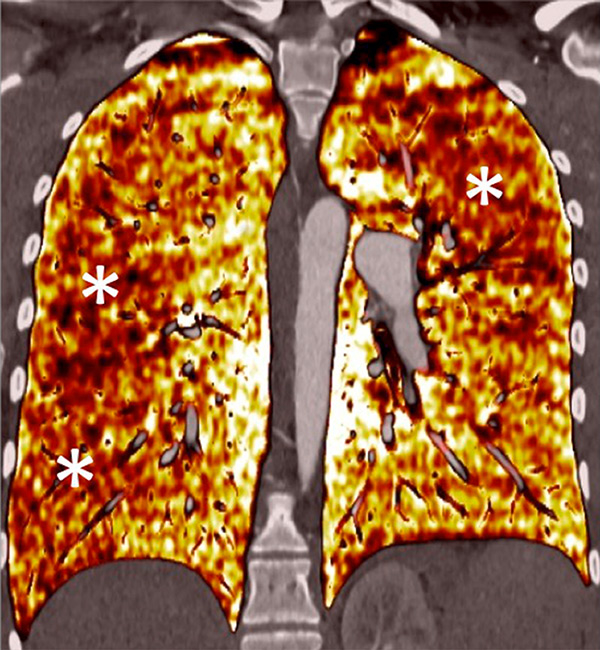

Figure 7

Portopulmonary hypertension in a 16-year-old. No abnormalities were found on morphological computed tomography (A/B), but heterogeneous perfusions were present on the perfusion map (stars, C/D).